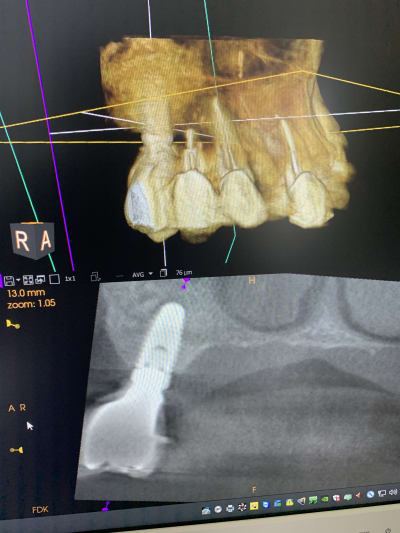

Il y a vraiment des différences de dingue entre les machines !

Les images 3 et 4, les images 6 et 7 sont prises à quelques années d’intervalles.

La machine de 2008 fait très peu d’artefacts, celle de 2018 énormément. Elle à le mar pour les « supprimer », mais ça n’arrange rien !

Les artefacts métalliques sont bien différents selon les machines.

A l’adf on me dit « regardez on voit même les spires des implants », avec ma bécanne de 2008 je vois les spires des vis dans les implants, les têtes de vis... je n’ai rien vu d’équivalent sur les machines récentes.

Regardez comme les tenons sont bien trop larges à la radio !

Les implants sont de gros pâtés blancs...